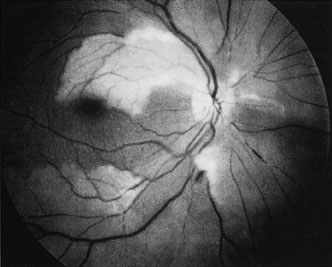

The clinical picture is typically striking. Patients present with a sudden painless loss of vision. The appearance of a cherry-red spot in the fundus is characteristic (Fig. 1).2 The cherry-red spot appears because soon after obstruction of the blood flow to the inner retina, the normally transparent retina becomes opaque and blocks the brownish-red color from the underlying choroid, which is still supplied by blood. Because the retina overlying the foveola is relatively thin, however, the normal color of the choroid is still visible in this area.3,4 Although characteristic, the cherry-red spot is not pathognomonic for central retina artery obstruction.5 Sometimes the characteristic cherry-red spot does not develop; there may be only a slight accentuation of the brownish-red color in the foveola.4 It is not known how long it takes this cherry-red spot to appear, but in a primate model, it has appeared as early as 30 minutes after obstruction.6 An afferent pupil defect is usually present.2

Fig. 1. A: Acute central retinal artery obstruction with a cherry-red spot. B and C: Intravenous fluorescein angiography. There is a delay of dye appearance in the central retinal artery, and when it does appear, it does not fill the arteries completely. D: Ocular coherence tomography (OCT) at the time of occlusion showing the increase in retinal thickness and reflectivity of the inner layers of the retina. E: Seven months later there is significant optic atrophy(G), and the OCT (F) shown now has marked thinning of the retina.

When a branch retinal artery is obstructed, there is usually whitening of the retina in the area supplied by the artery (Fig. 2). In most eyes (62% in one series), emboli are responsible for the obstruction.94 The temporal branch arteries are involved in almost all cases that have been reported,92,94 but whether this is because nasal branch retinal artery obstructions are rare or because such obstructions are simply asymptomatic is unknown. The characteristics of a branch retinal artery obstruction on intravenous fluorescein angiography are similar to those for central retinal artery obstruction.

Fig. 2. Multiple branch retinal artery obstructions in a young woman with encephalopathy and hearing loss. (Photograph courtesy of Jack W. Pierce, M.D.)